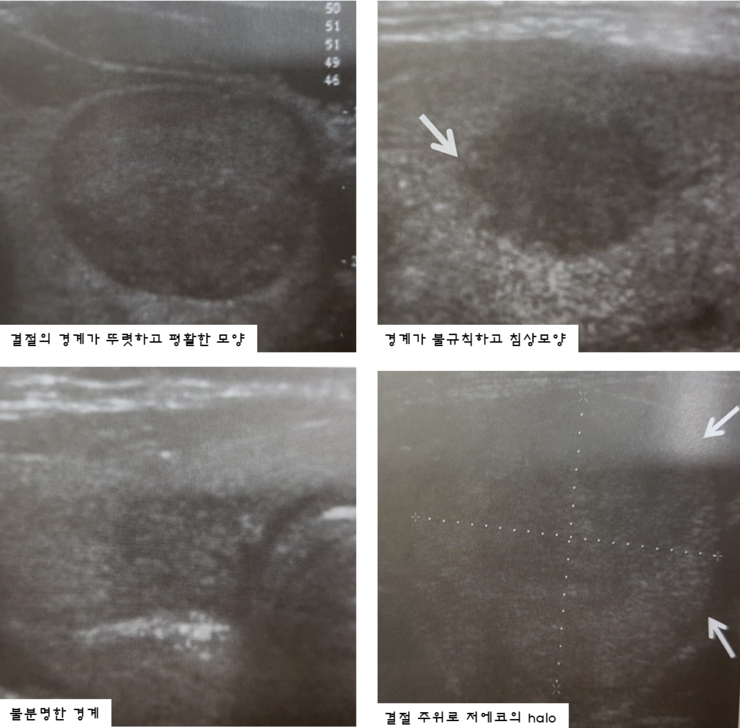

갑상선 석회화 결절의 진단은 갑상선 초음파로 결절의 위치, 개수, 모양, 크기, 내부, 비율, 경계 등을 자세히 관찰하는 것이다. 이로부터 이상이 발견되면 악성의 위험성을 예측할 수 있고 세침흡인세포검사를 시행할 수 있다. 동시에 정상적인 갑상선 기능을 확인하기 위해 혈액 검사를 실시합니다. 그러나 갑상선 초음파에서 갑상선에 석회화된 결절이 보인다고 해서 반드시 갑상선암으로 진행되는 것은 아닙니다. 첫째, 갑상선 결절의 크기가 5mm 이상인 경우 추가 생검이 필요합니다. 그러나 갑상선 석회화가 많이 진행된 경우에는 조직세포 채취에 어려움이 있을 수 있습니다.의정부갑상샘선 김수연유한의원